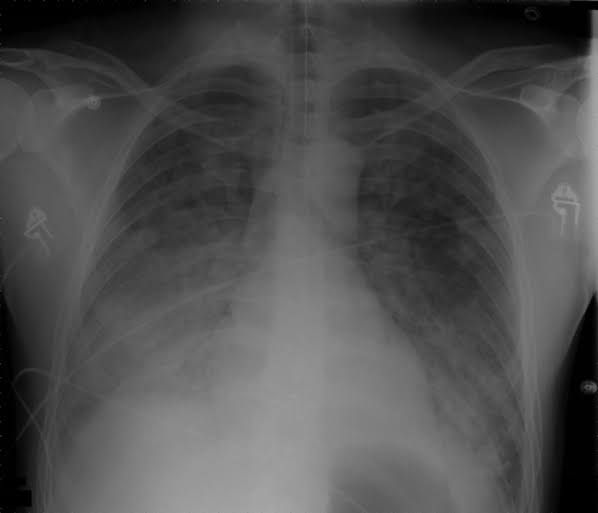

Acute Respiratory Distress Syndrome is a form of non-cardiogenic pulmonary edema due to diffuse alveolar damage. According to Berlin criteria ARDS is defined by timing (within 1 week onset of respiratory symptoms), radiographic changes (bilateral opacities not fully explained by effusion, consolidations, or atelectasis), origin of edema (not fully explained by cardiac failure or fluid overload) and severity based on the PaO2/FiO2 ratio on 5 cm of CAP.